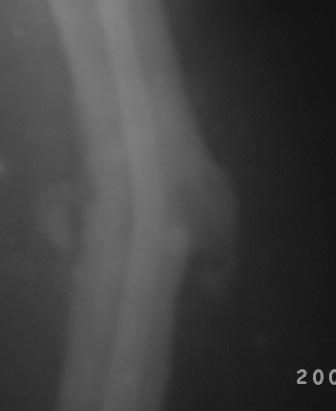

Уважаемые коллеги! Обратилась б-ная 1982г.р. 2008г. в апреле оперирована в одном солидном мед.учреждении, и/м остеосинтез штифтом лев.бедра ( похоже Кюнчером), в то время была беременной, через месяц выкидыш.

Со слов около 6 мес. коксит.гипсов. повязка,и до сих пор ходила с двумя костылями, кормили многими лекарствами как остеогенон. бонвива и мн. другими и даже гормонами. поправилась на 15-20кг. Но активно ногу могла поднять на 4 пальца от пола и не надолго.01.02.09.г упала на правую бок, с тех пор резкая боль в обл бедра, боиться шевелить ногой, не дает пальпировать,обратилась к леч.врачу, предлагали костно-пластическую операцию , после обратилась к нам.

При тщательном исследовании выясняется что все таки имееться положительная динамика, боли уменьшается, при отвлечении можно двигать ногами, признаков рефрактуры нет, умеренная равномерная отечность, боли в мягких тканях, в надвертельной обл. боли нет, конец штифта не прошупивается. Мышцы бедра атрофированы, слабые. И на Р-гр я не вижу рефрактуру!

Мой план, покой, анальгетики, УВЧ, антидепрессанты, после активация, пусть походить костылями потом без оних, реабилитация. После польной восстановлении решить вопрос удалении штифта.

В отд. идет дискуссия по поводу рефрактуры, и о удалении штифта.